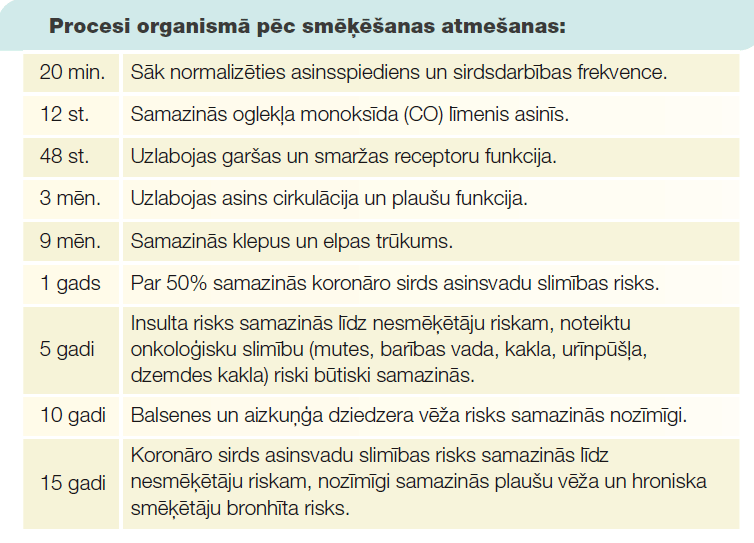

Plaušu vēža attīstības riska samazināšanai svarīgākais faktors ir smēķēšanas atmešana. Savukārt, plaušu vēža skrīnings dod iespēju slimību atklāt agrīni un tādējādi sasniegt labākus ārstēšanas rezultātus.

Smēķēšanas atmešana

Tabakas produktu smēķēšana ir galvenais plaušu vēža riska faktors. Vairāk kā 80% plaušu vēža slimnieku ir esoši vai bijušie smēķētāji. Tāpēc ir ļoti svarīgi smēķēšanu neuzsākt vispār vai to pēc iespējas ātrāk atmest. Tabakas dūmos ir identificētas vismaz 50 potenciāli kancerogēnas vielas, kuras skar elpceļus izklājošas šūnas. Dažas no šīm vielām ir radioaktīvas, dažas ir indes.

stipru psiholoģisku atkarību. Smēķēšanas atmešana var būt saistīta ar tādām izpausmēm kā dusmas, trauksme, koncentrēšanās grūtības, miega traucējumi. Šie simptomi visstiprāk izpaužas 2–4 nedēļas pēc smēķēšanas pārtraukšanas, bet vēlāk pakāpeniski pāriet. Smēķēšanas atmešanai ir pieejami palīglīdzekļi – nikotīna aizstājterapija, psihoemocionālais atbalsts, specifiski medikamenti. Latvijas

iedzīvotājiem ir pieejamas telefona konsultācijas smēķēšanas atmešanai, informāciju par tām var atrast slimību profilakses un kontroles centra mājaslapā (spkc.gov.lv). Par specifiskiem medikamentiem runājiet ar savu ārstējošo ārstu. Smēķēšanas atmešana ir ļoti svarīga gan plaušu vēža novēršanai, gan plaušu vēža ārstēšanas efektam!